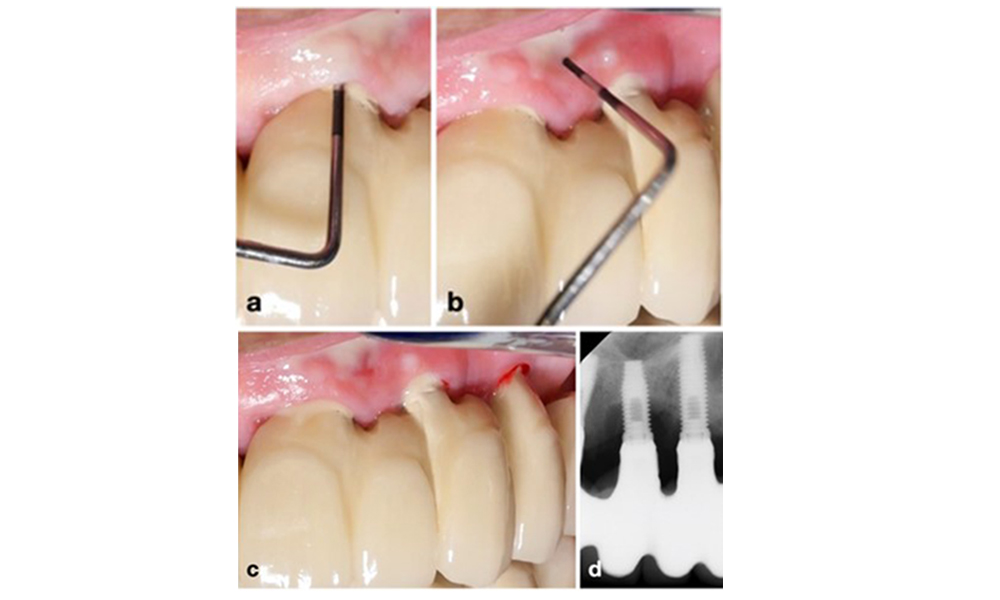

Peri-implantitis is identified by (1) signs of inflammation similar to mucositis, (2) radiographic evidence of bone loss after initial healing and (3) an increase in probing depth compared to measurements taken shortly after placing the prosthetic reconstruction (figure 2). In the absence of previous radiographs, radiographic bone level of ≥ 3 mm along with bleeding on probing and probing depths ≥ 6 mm, indicates peri‐implantitis.

Full-arch restoration with peri-implantitis of varying degrees at some implants. The implant in position 21 is severely affected with probing depths up to 9 mm (a), bleeding on probing, and suppuration from the peri-implant sulcus and a vestibular fistula (b–c); the radiograph shows approximately 50 % bone loss for the implant with peri-implantitis in position 21, while the implant in position 23 shows limited bone loss, corresponding approximately to what can be expected after initial healing for this type of implants (d).

Figure 2. Full-arch restoration with peri-implantitis of varying degrees at some implants. The implant in position 21 is severely affected with probing depths up to 9 mm (a), bleeding on probing, and suppuration from the peri-implant sulcus and a vestibular fistula (b–c); the radiograph shows approximately 50 % bone loss for the implant with peri-implantitis in position 21, while the implant in position 23 shows limited bone loss, corresponding approximately to what can be expected after initial healing for this type of implants (d).

The expected bone loss after initial healing attributed to marginal bone remodelling, varies based on factors such as the implant system or type. For instance, 1–2 mm bone loss is generally considered “normal” for bone level implants with an external connection (figure 2d, implant in position 23).